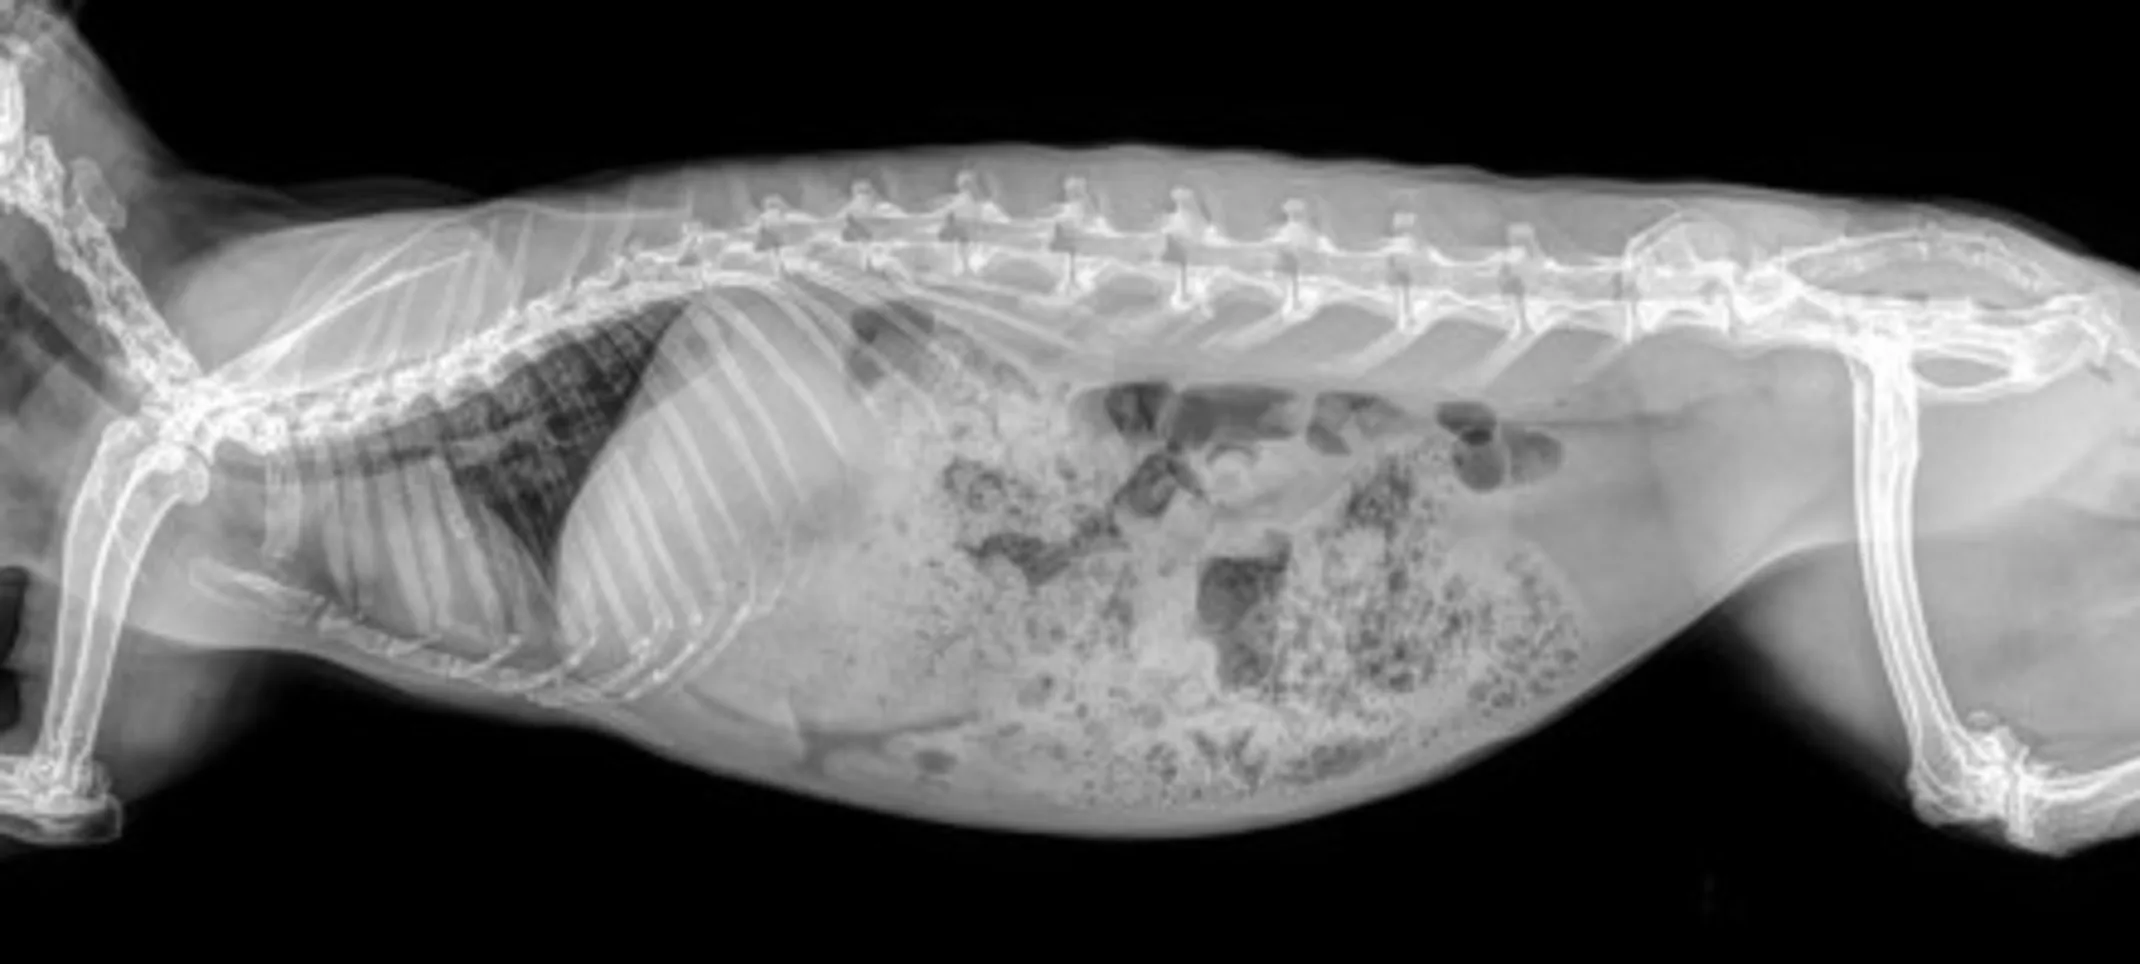

Veterinary radiology – radiographs and ultrasounds – help diagnose and treat many diseases in animals.

They help plan further diagnostic plans, such as whether to take a biopsy and how best to take the sample. They help detect diseases early, before your pet may shows signs. We see effective early detection of bladder stones, disc disease, joint disease and heart disease on a weekly basis. Radiographs and ultrasounds also help us design treatment plans when your pet is sick. Examples include how to fix a broken or dislocated limb, where a foreign object is lodged, or if your coughing pet has asthma, pneumonia or tracheal collapse.

Gestational radiographs